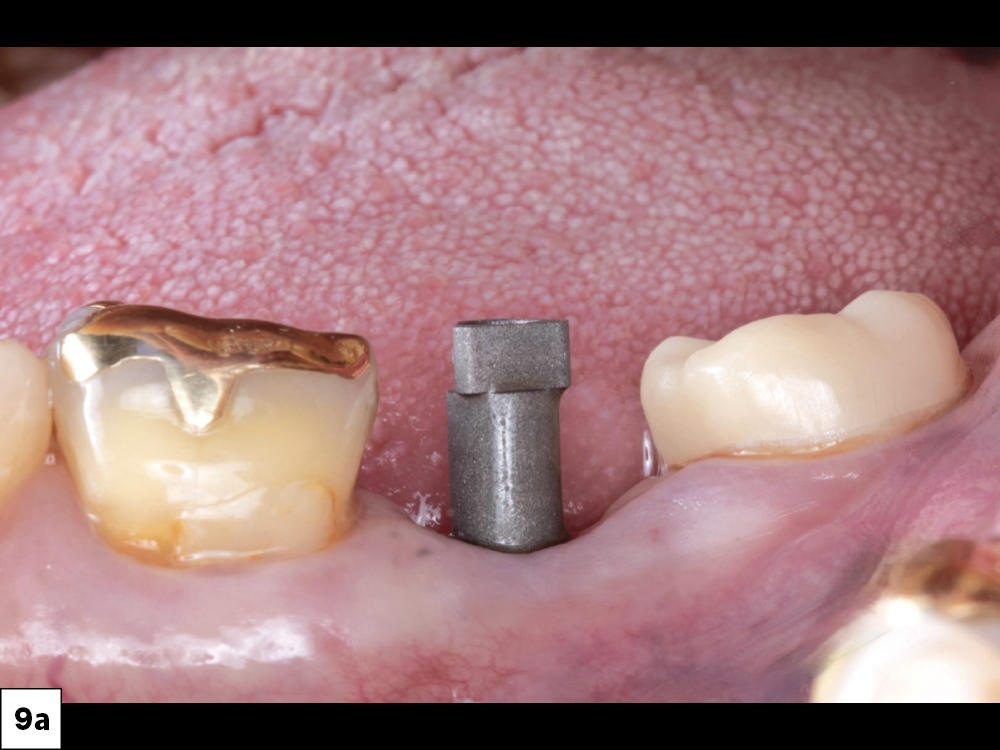

In-office milling is a quickly evolving option for the modern dental practice. With the introduction of a same-day screw-retained option, BruxZir® NOW SRC milling blocks, there’s even more opportunity for optimizing single-unit restoration workflows. In this case study, I’ll demonstrate how this product can be used as part of an efficient workflow for tooth replacement in the posterior. When combined with guided surgery and in-office crown design, this procedure offers reliable results while saving money and significantly cutting down on chair time for dentists.